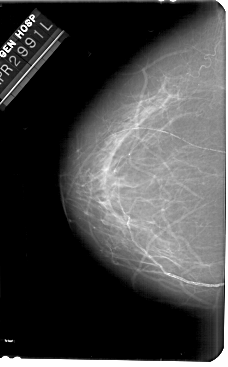

A_1681_1.LEFT_MLO

LEFT_MLO LINES 5491 PIXELS_PER_LINE 3526 BITS_PER_PIXEL 12 RESOLUTION 43.5 NON_OVERLAY